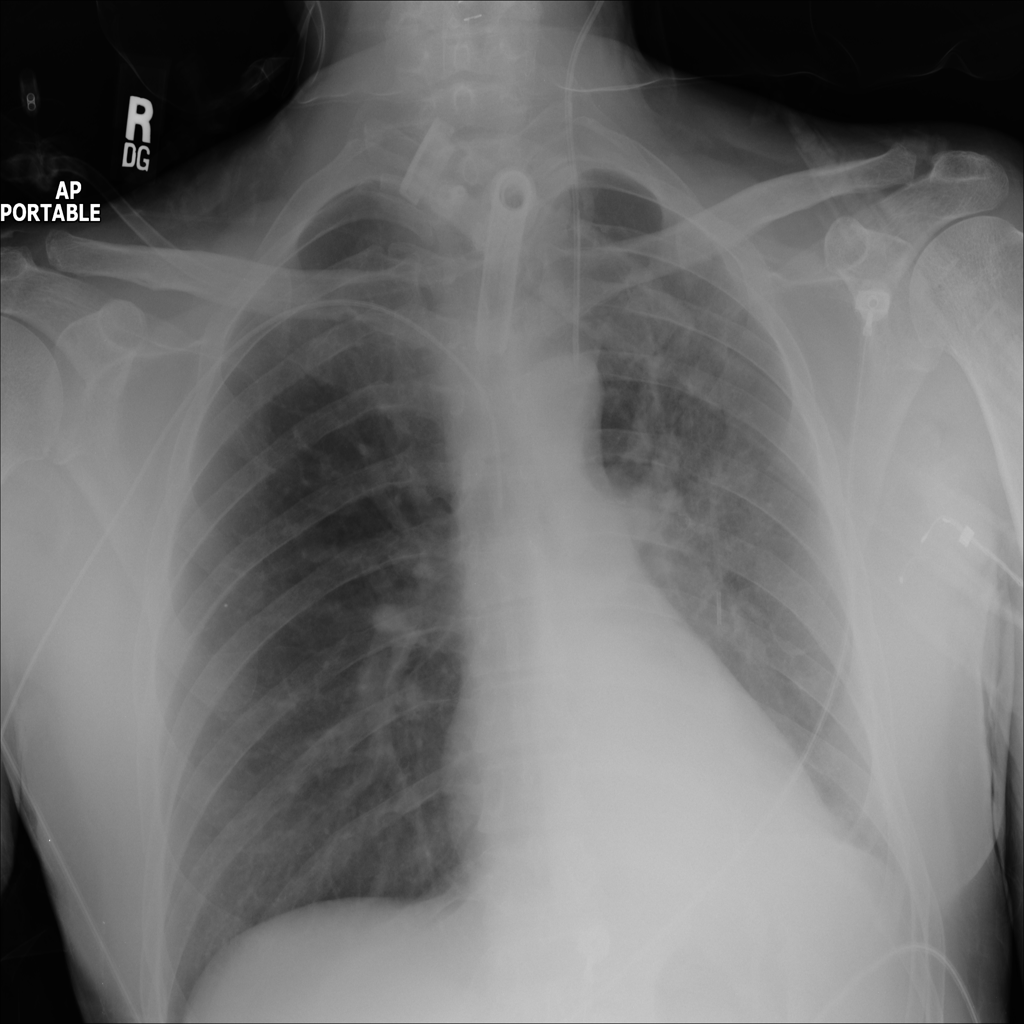

PAT-64EB · IMG-015Consolidation

PAT-64EB · IMG-015

AP